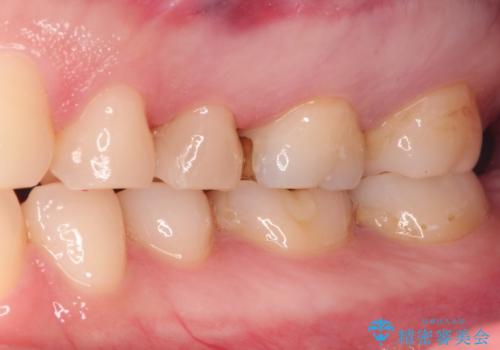

古い材料を除去すると中で虫歯が進行していたため、顕微鏡下で虫歯を除去した後セラミックインレー、PGAインレーにて修復治療を行いました。